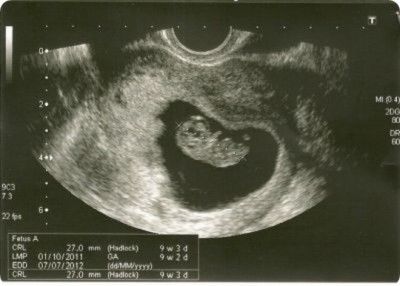

На 20 тижні вагітності чітко видно різницю між хлопчиком і дівчинкою в утробі матері. У міру зростання і розвитку малюка така різниця стає ще виразніше і на УЗД в 3 триместрі вагітності чітко видно: народитися син або дочка. Але за умови, що на момент ультразвукового дослідження навколо малюка буде потрібну кількість навколоплідних вод, що він не перехрестить свої ніжки. А таке трапляється досить часто!

Медична статистика свідчить, що ймовірність помилки існує завжди. Дослідження точності визначення статі показали, що навіть при правильній позі дитини в момент УЗД досвідчені лікарі та сучасне обладнання визначають стать на терміні одинадцять тижнів з точністю до 70%. Коли ж термін зростає до дванадцяти тижнів, то точність становить дев'ять випадків з десяти.

Найостанніші дослідження говорять про те, що на терміні 12 тижнів точність діагностики статі по УЗД становить 46%, на терміні 13 тижнів - 80%.

Точно дізнатися стать майбутньої дитини на першому УЗД навряд чи вдасться. Сьогодні апарати ультразвукового дослідження не настільки високотехнологічні, щоб точно можна було розгледіти статеві ознаки плода. І до всього цього, лікар не буде чекати довго, поки малюку захочеться перевернутися і зайняти зручну для лікаря позу. До речі, на 13 тижні терміну дитина вже так крутиться в лоні майбутньої мами, що зловити потрібний доктору кут дуже складно.

На УЗД, якщо дитина добре повернувся, підлога може бути визначений на терміні 12 тижнів після зачаття (14 акушерських).